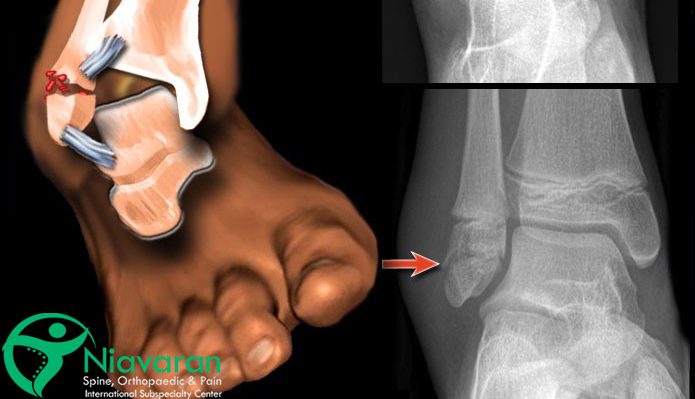

مهمترین و اصلیترین گزینه برای تشخیص شکستگی قوزک پا، عکس رادیولوژی ایکس ری است. در عکس شکستگی مچ پا، صرفاً بافتهای استخوانی قابل رویت است؛ بنابراین برای تشخیص پیچ خوردگی یا شکستگیهای بسیار کوچک باید از تصویربرداریهایی با جزئیات بیشتر مثل MRI و سیتیاسکن استفاده شود.

معاینات فیزیکی و بررسی علائمی مانند تورم، کبودی، حساسیت و درد بسیار شدید، عدم توانایی در راه رفتن و خارج شدن فرم پا از حالت عادی نیز، میتواند به تشخیص کمک کند؛ اما همچنان عکس رادیولوژی ایکس ری رایجترین راه برای تشخیص است.

- تصویربرداری اشعه ایکس ری: تصویر رادیولوژی، میزان و نوع شکستگی را بهخوبی نشان میدهد.